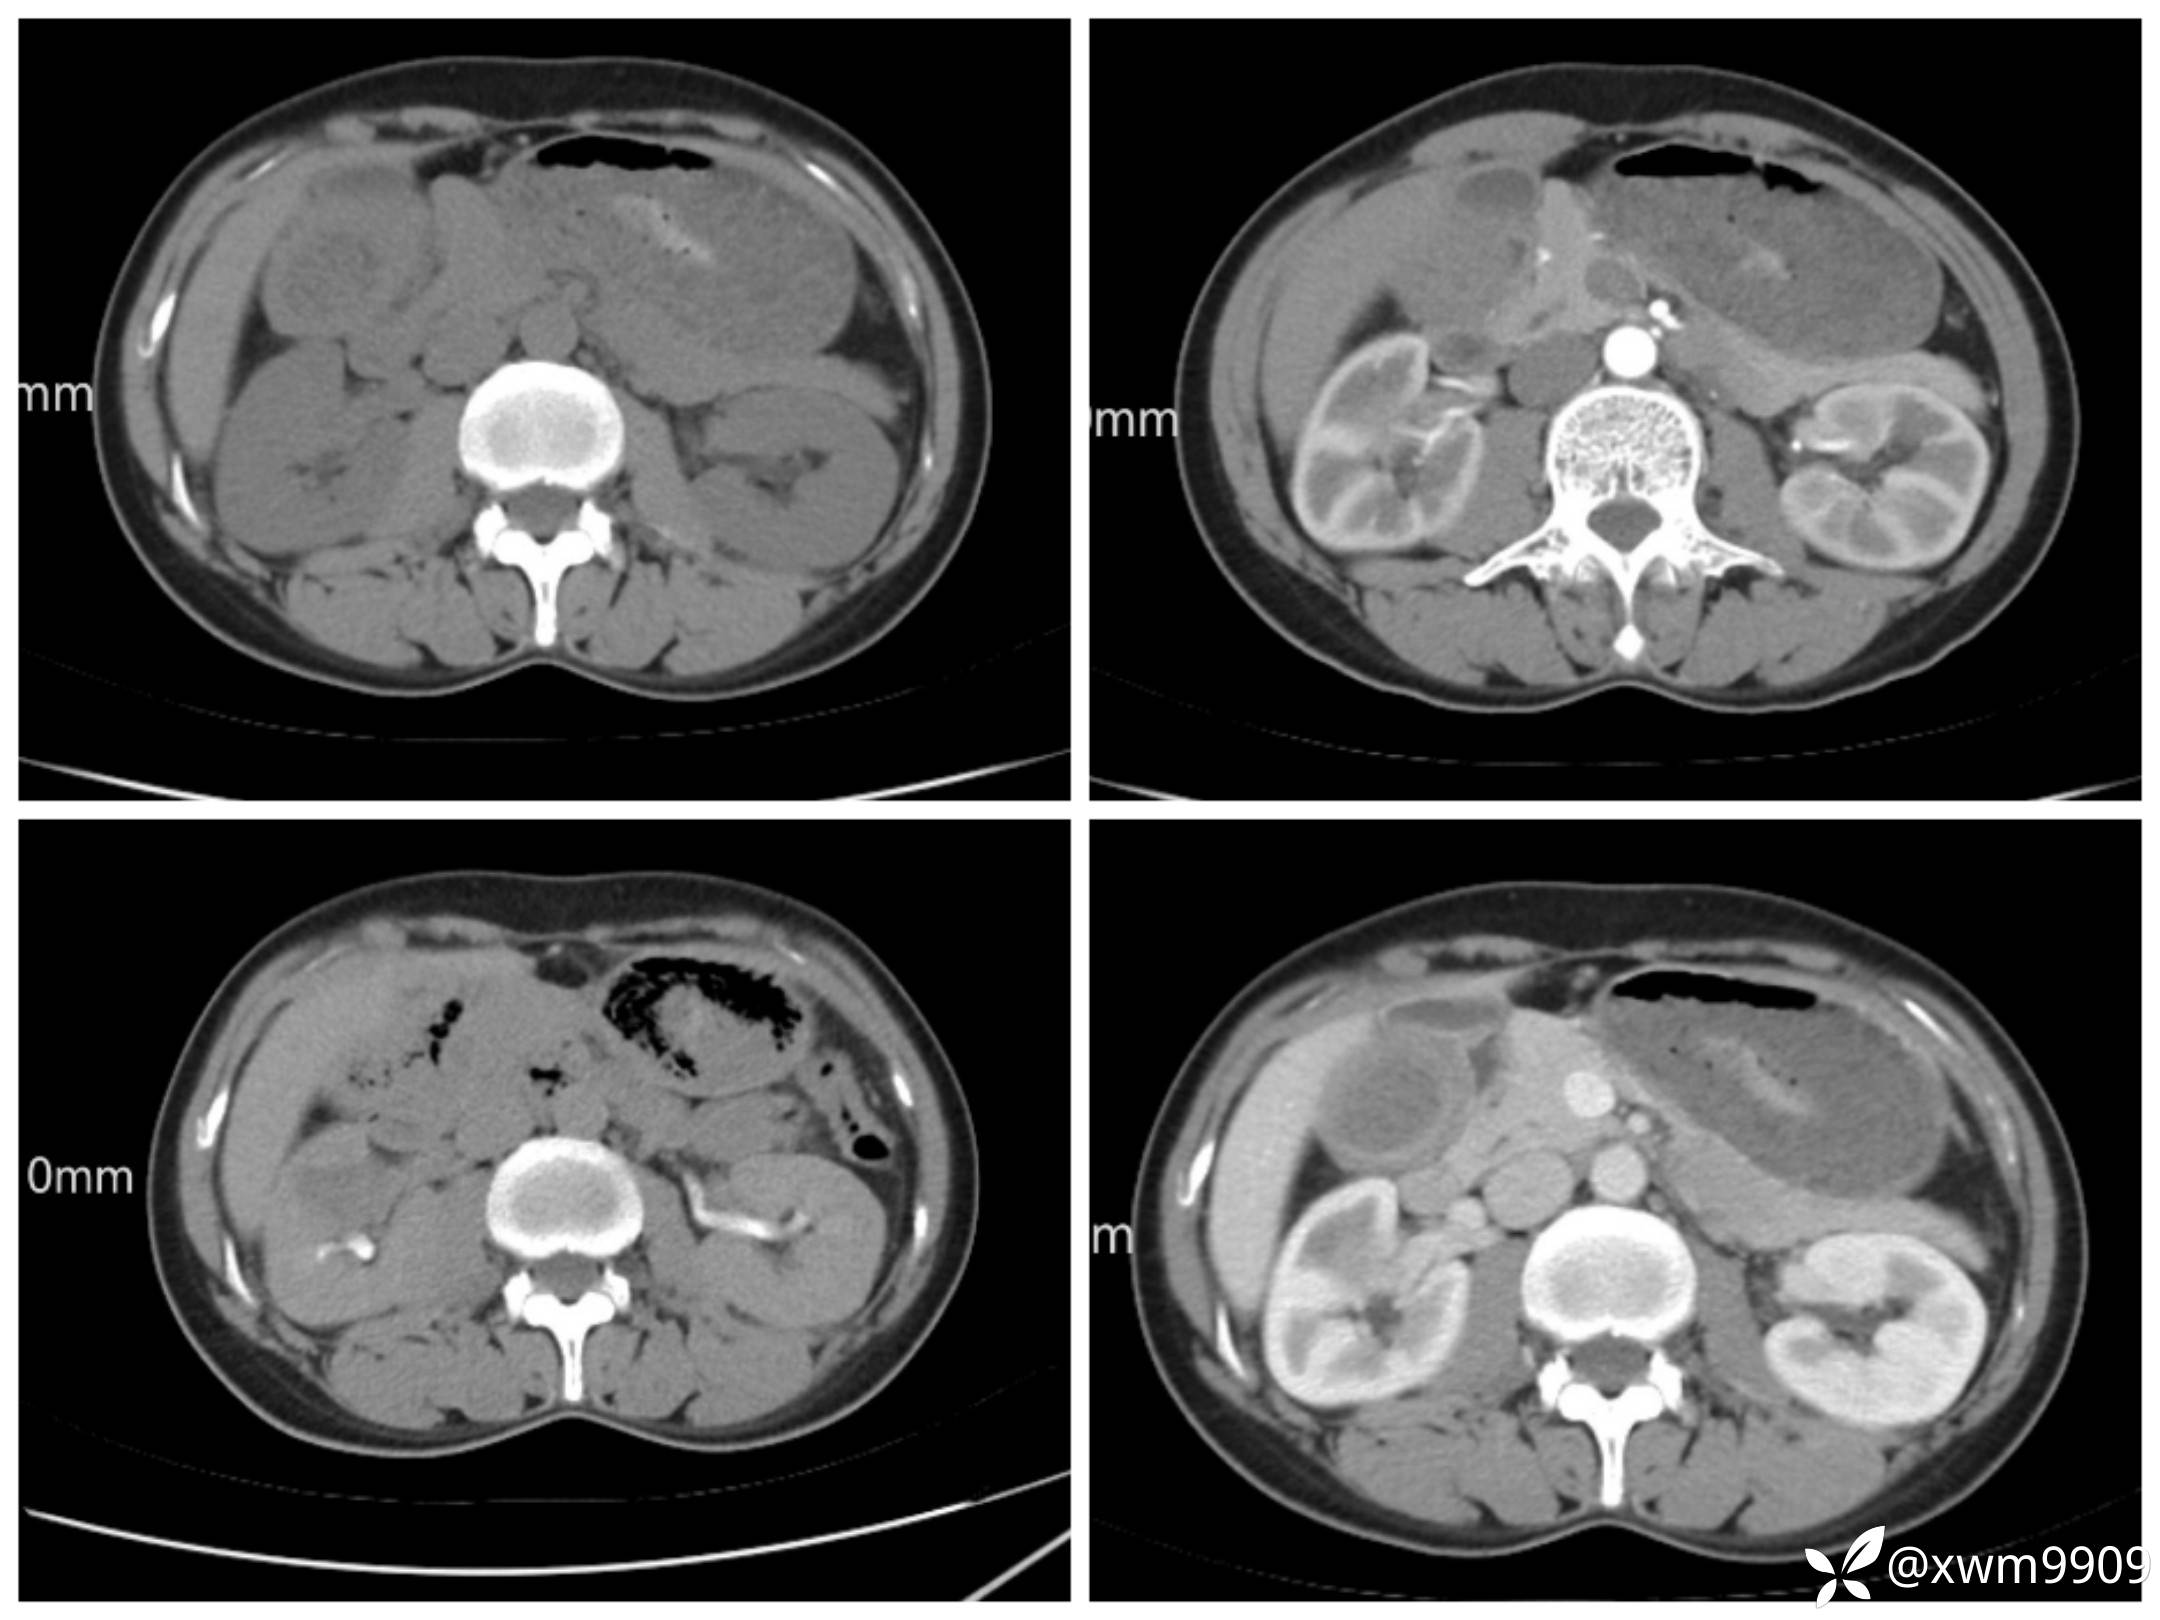

3、AFP、CEA、CA72 -4、CA50、CAl9-9。

T2:

反相位:

同相位:

LAvA:

A:

v:

平衡期:

DwI丶ADC: